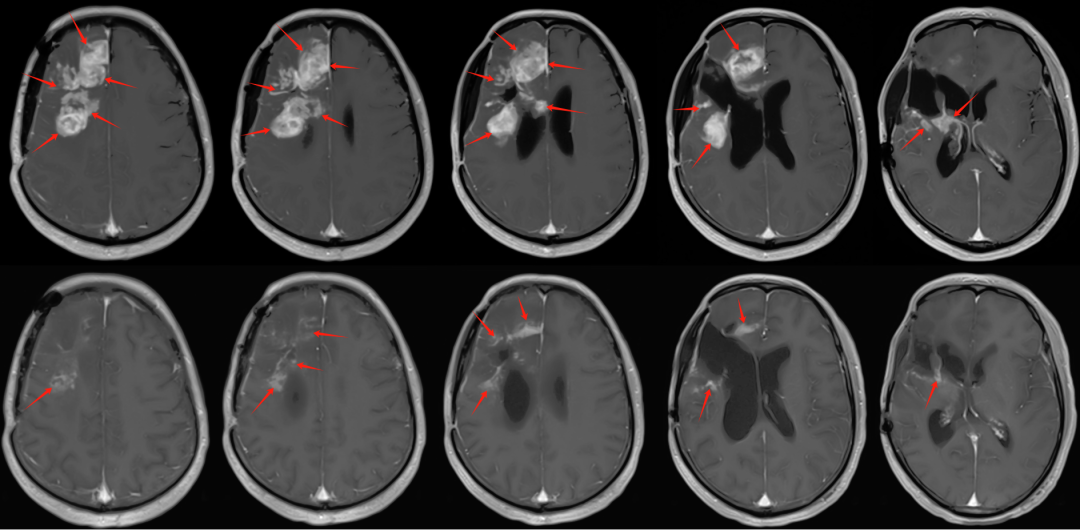

圖注:頭部磁共振檢查。可見(jiàn)復(fù)發(fā)腫瘤位于右側(cè)額顳葉,右側(cè)側(cè)腦室,以及右側(cè)基底節(jié)區(qū)受累及,病灶體積大。局部壓迫功能區(qū)造成患者左側(cè)肢體癱瘓。

腦膠質(zhì)母細(xì)胞瘤(WHO Ⅳ級(jí))是原發(fā)中樞神經(jīng)系統(tǒng)惡性腫瘤中,惡性程度最高,預(yù)后最差的腫瘤,術(shù)后易復(fù)發(fā)。該患者磁共振檢查顯示,復(fù)發(fā)腫瘤位于右側(cè)額顳葉,基底節(jié)區(qū)受累及,體積巨大,為治療帶來(lái)巨大困難。患者腫瘤范圍大,侵犯?jìng)?cè)腦室,基底節(jié)區(qū),手術(shù)難度及風(fēng)險(xiǎn)大。患者術(shù)后僅6個(gè)月,在應(yīng)用輔助化療期間,即發(fā)生復(fù)發(fā)。即使再次手術(shù),短時(shí)間內(nèi)仍會(huì)復(fù)發(fā)。且患者身心上也無(wú)法接受短期內(nèi)再次開(kāi)顱手術(shù)。此外,腫瘤病灶巨大,復(fù)發(fā)膠質(zhì)母細(xì)胞瘤對(duì)放射治療較抗拒,放射治療效果往往不理想。且患者基因檢測(cè)結(jié)果顯示患者預(yù)后不良,缺少有效的治療藥物,此類患者治療非常棘手。